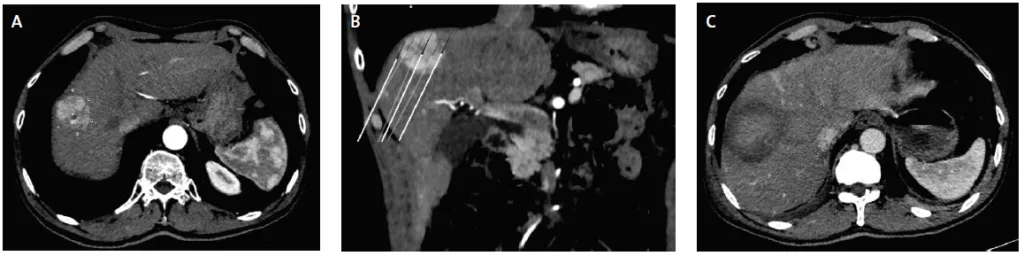

Figure 3. Ablation radiofréquence multibipolaire d’un volumineux CHC de 5,5 cm (mass forming) du dôme hépatique

A. TDM axiale,

B. et frontale au temps artériel de l’injection intraveineuse de produit de contraste iodée montrant une masse du segments 8. Le planning du positionnement des six électrodes est figuré par des overlays (en section en A du fait de la trajectoire ascendante des électrodes). Noter que 5 électrodes sont positionnées en dehors autour de la masse et qu’une seule est insérée au centre afin d’assurer la continuité de l’ablation (technique convergente centripète. Voire aussi la Figure 1)

C. Tomodensitométrie de contrôle un mois après au temps artériel de l’injection intraveineuse de produit de contraste iodé. La zone d’ablation englobe parfaitement l’ancienne masse du segments 8 (compte tenu de la proximité du diaphragme une ascite artificielle de protection avait été créée avant le dépôt d’énergie).